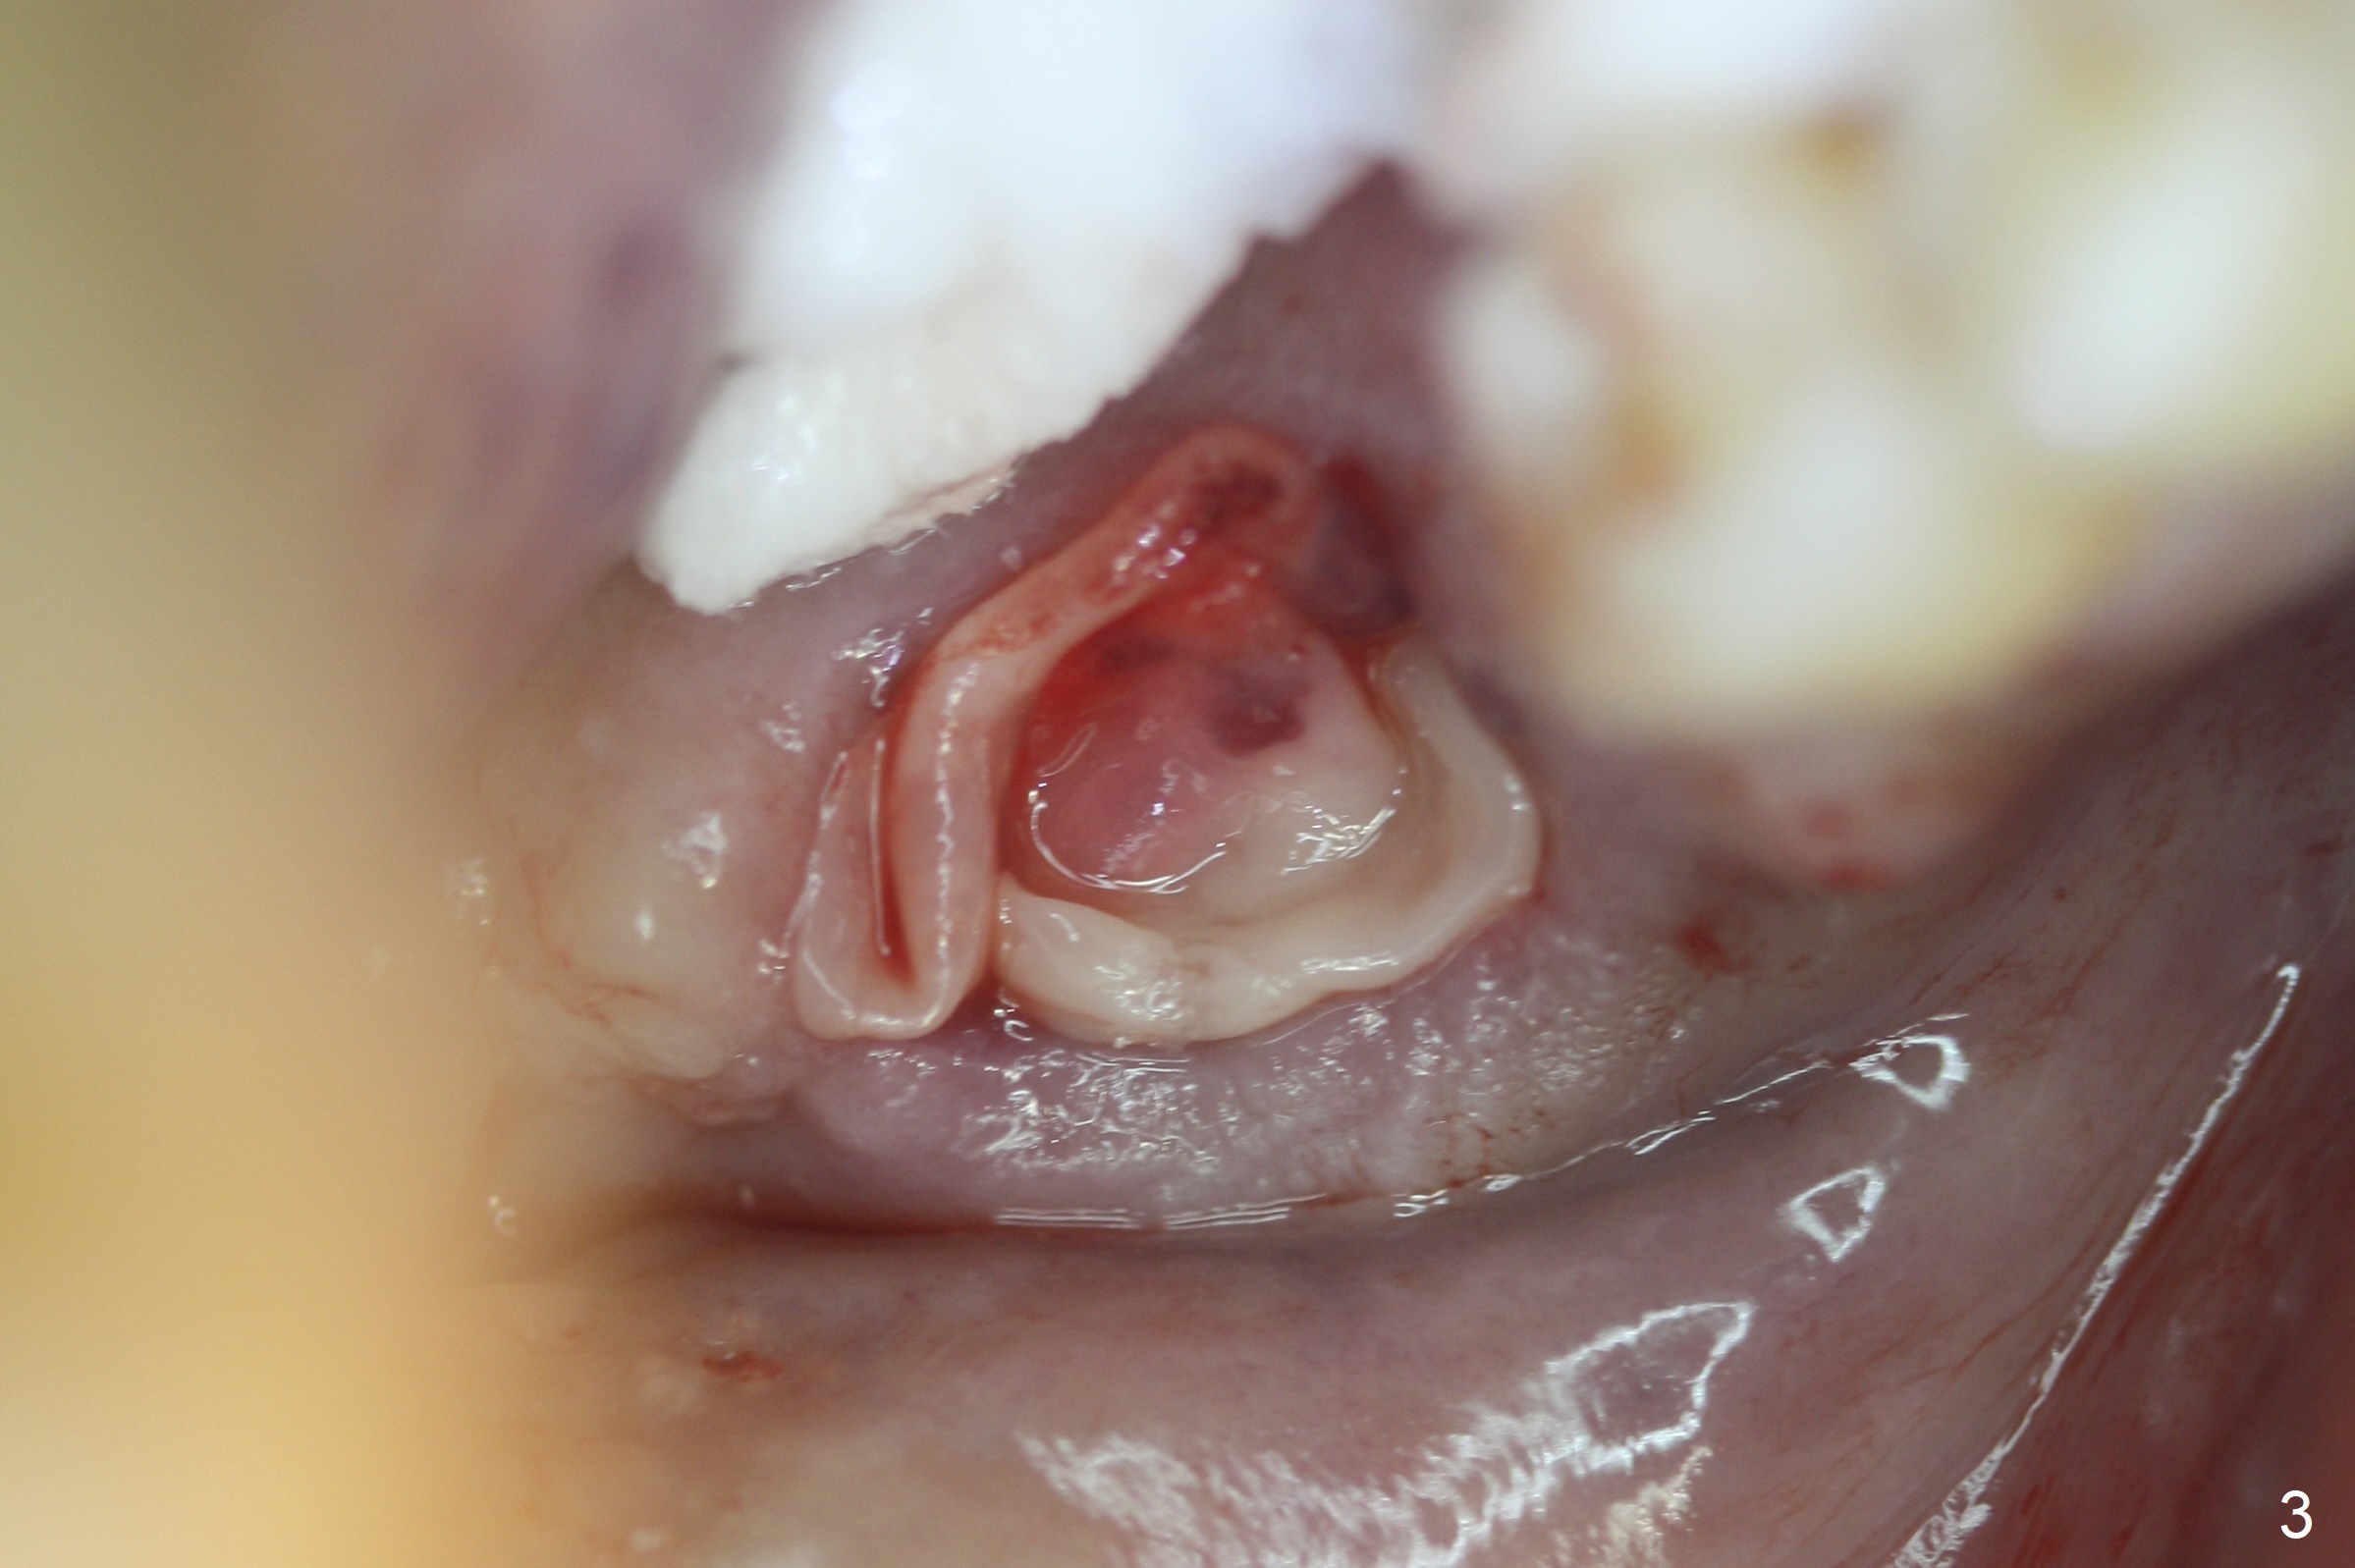

Extraction of the mobile tooth #31 (Fig.1) and debridement of the large socket are not difficult. But making osteotomy buccally does not seem to be easy. It will be difficult to restore. Instead, socket preservation is accomplished by filling the socket with approximately 1.5 cc of Mineralized Cortical/Cancellous allograft until the crest (Fig.2,5). The socket opening is closed by insertion of 4 pieces of PRF membranes (Fig.3) and 4-0 Chromic gut sutures (Fig.4). In the end of surgery, it appears that osteotomy in the center of the socket could be a better approach. Postop re-analysis of CT (Fig.6) and PA (Fig.7) shows that there is 3.9 mm of the native bone to support a 5.5x10 mm implant. Sinus Lift Master Kit should be used with 2 mm initial drill and 2.8 and 3.6 mm round drills with 4 mm stopper.